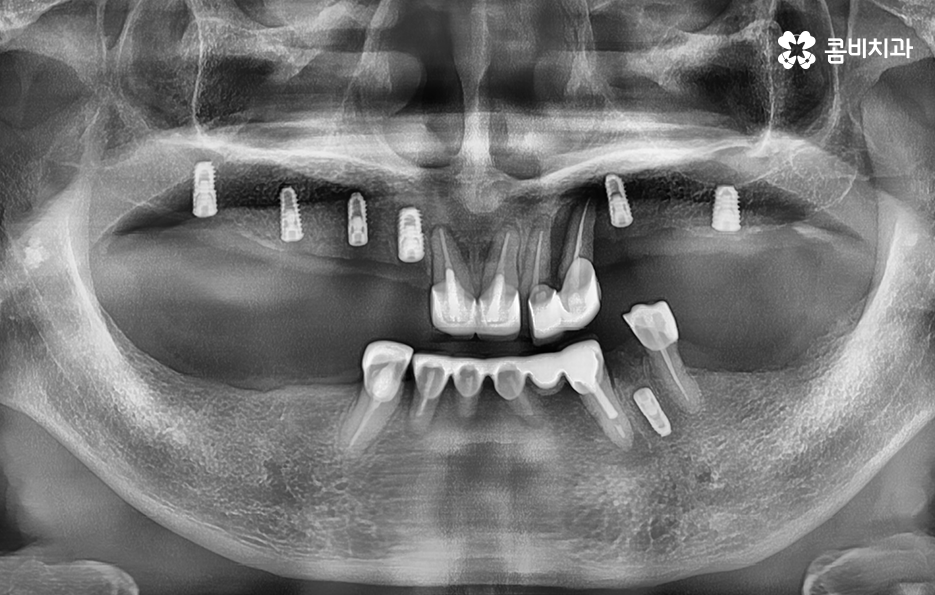

반면에 5,60대 이후에는 치주질환으로 인해 치아를 잃게 되는 경우가 많고 잇몸이 약해진 상태이거나 전신질환 등을 함께 고려해야 하는 복합적인 치료 계획을 세워야 하는 경우가 좀더 많이 있는데요

실제 치료 사례를 살펴보더라도 젊은 환자분들의 경우 원데이임플란트로도 치료가 가능한 사례가 많다면 노인분들의 경우 잇몸이 약해진 상태에서 치주염으로 치아를 잃게 된 경우가 많다보니 뼈이식을 추가적으로 받아야 하는 경우가 많이 있어요

정리하면 임플란트 나이 단순히 나이만으로 치료 계획에 대해 쉽게 판단하기는 어렵겠지만 통계적으로 볼 때 치아의 주된 상실 원인과 임플란트의 원리에서 잇몸 뼈의 중요성을 따져볼 때는 젊은 환자분들에 비해 60대 이후 환자분들이라면 뼈이식을 추가로 받아야 한다거나 회복력과 전신질환에 대해서도 충분히 좀더 감안하여 치료 계획을 디테일하게 세울 필요가 있다는 것을 알 수 있는데요